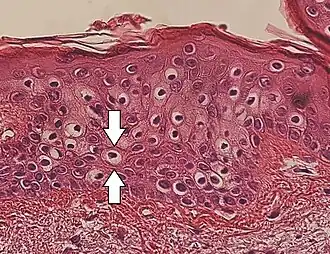

Perinuclear vacuolization of epidermal keratinocytes (one indicated by arrows), in this case an insignificant incidental finding.

Vacuolization is the formation of vacuoles or vacuole-like structures, within or adjacent to cells. Perinuclear vacuolization of epidermal keratinocytes is most likely inconsequential when not observed in combination with other pathologic findings. In dermatopathology "vacuolization" often refers specifically to vacuoles in the basal cell-basement membrane zone area, where it is an unspecific sign of disease.[1] It may be a sign of for example vacuolar interface dermatitis, which in turn has many causes.